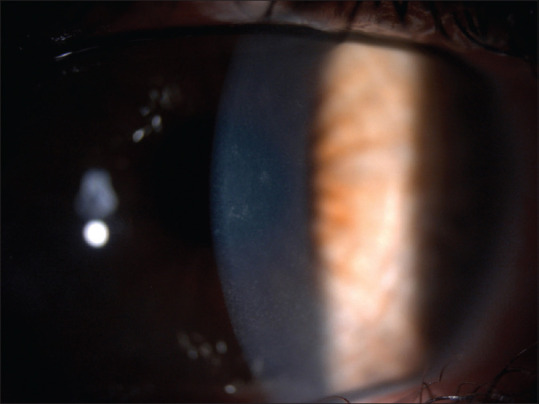

5-氟尿嘧啶(5-FU)是治疗结膜和角膜发育不良的重要化疗辅助药物。由于这种药剂有可能进入前房,因此有多篇文献报道证实了 5-FU 的长期安全性和有效性。虽然最近有文献报道局部使用 5-FU 对角膜内皮没有细胞毒性作用,但我们报告了一名双侧眼表鳞状上皮瘤患者在开始使用 5-FU 疗程后,角膜内皮密度和形态发生了显著变化。

5-fluorouracil (5-FU) is an important chemotherapy adjunct for the management of conjunctival and corneal dysplasia. Since it is possible for this agent to gain access to the anterior chamber, several reports in the literature have demonstrated 5-FU long-term safety and efficacy. Although recent publications reported that topical 5-FU has no cytotoxic effect on the corneal endothelium, we report a patient affected by bilateral ocular surface squamous neoplasia who has developed significant endothelial density and morphology changes after starting a course of 5-FU.